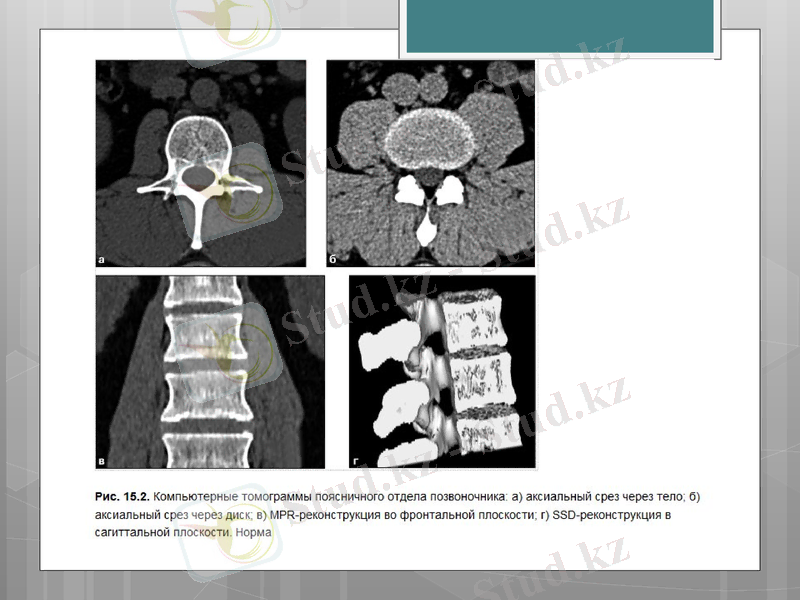

Рентгендік компьютерлі томография

КТ сканирлеудің барлық қашықтығында омыртқаның әртүрлі құрылымдарының қабаттық көріністерін алуға мүмкіндік береді, соның ішінде паравертебральды аймақтың жұмсақ тіндері, трабекулярлы және қыртысты қабаттарымен сүйек құрылымдары, құрамында май тіні бар жұлын өзегі, жұлын, дүйке түйіндері, жұлын-ми сұйықтығы.

Спиральды режимдегі КТ-зерттеу омыртқа жарақаты бар науқастарда диагностиканың қолайлы әдісі болып есептеледі. Сүйек құрылымдарының, аралас мүшелер мен тіндердің барлық анатомиялық өзгерістерін сипаттауға және дуральды қаптың жағдайын бағалауға болады.